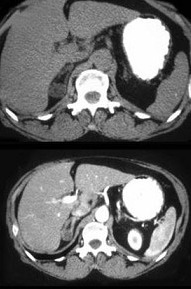

女,35岁,无意中发现血压高,实验室检查:血和尿中醛固酮水平增高,请结合所提供图像,作出诊断( )

A:右肾上腺增生

B:右肾上腺Cushing腺瘤

C:右肾上腺皮质腺瘤

D:右肾上腺转移瘤

E:右肾上腺囊肿